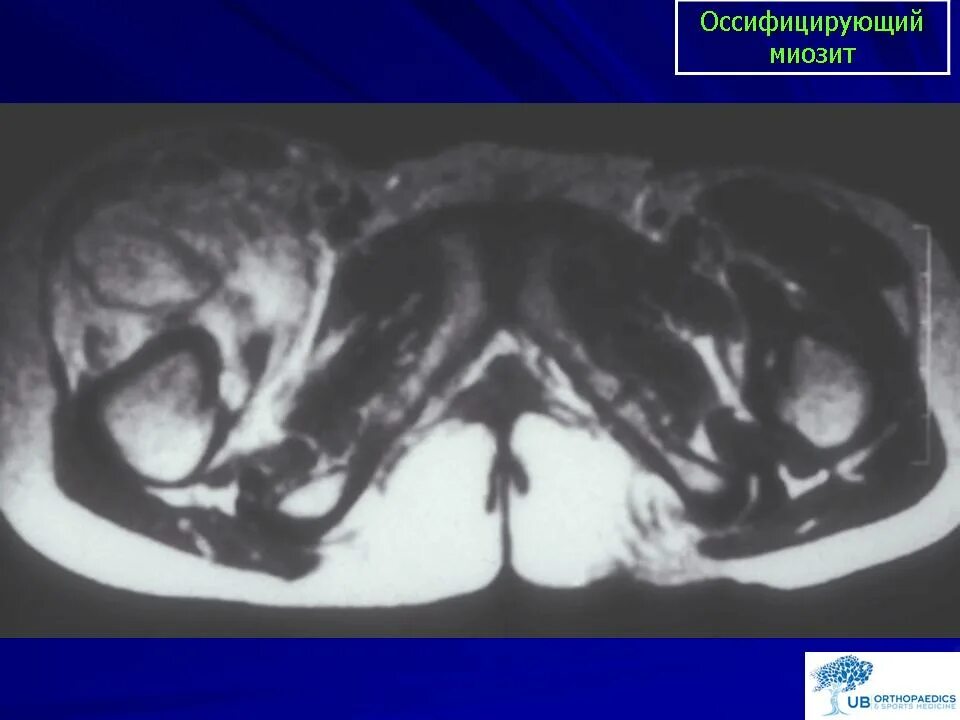

Оссифицированный миозит